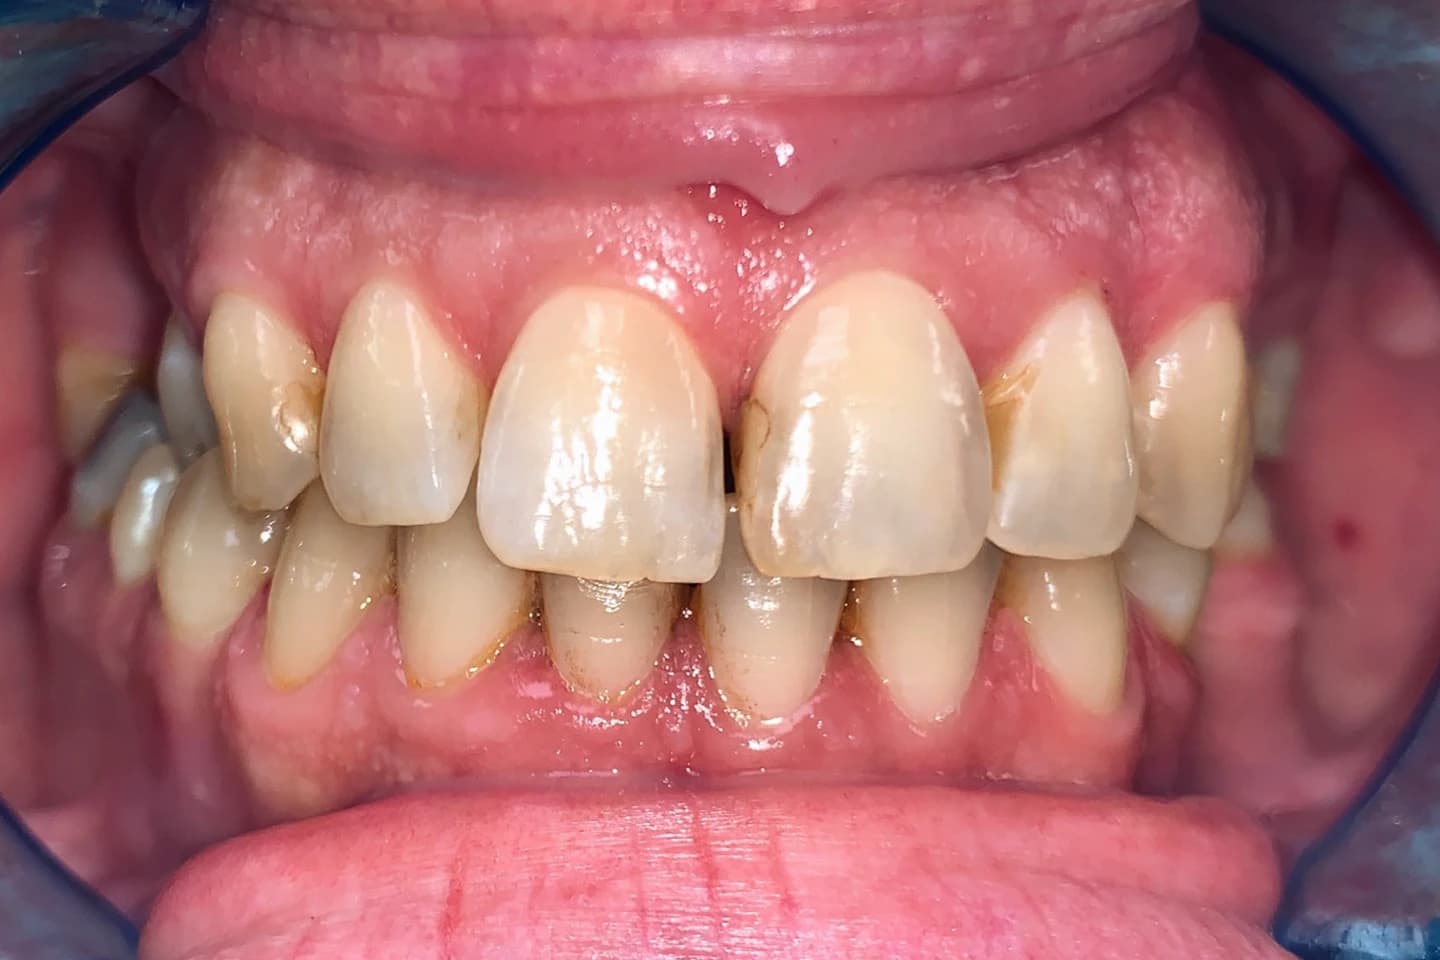

Osmeh i oblik zuba slike - pre i posle

Stomatološka ordinacija Marco Dental Tourism svakodnevno stvara neverovatne transformacije osmeha. Pogledajte galeriju naših radova i uverite se u moć stomatologije!

Želimo i vama da pomognemo da postignete savrršen osmeh kada su u pitanju položaj i oblici zuba. Zato smo prikupili inspirativne priče i fotografije zuba naših pacijenata, koje će vam pokazati šta je sve moguće uz stručnost i posvećenost našeg tima.